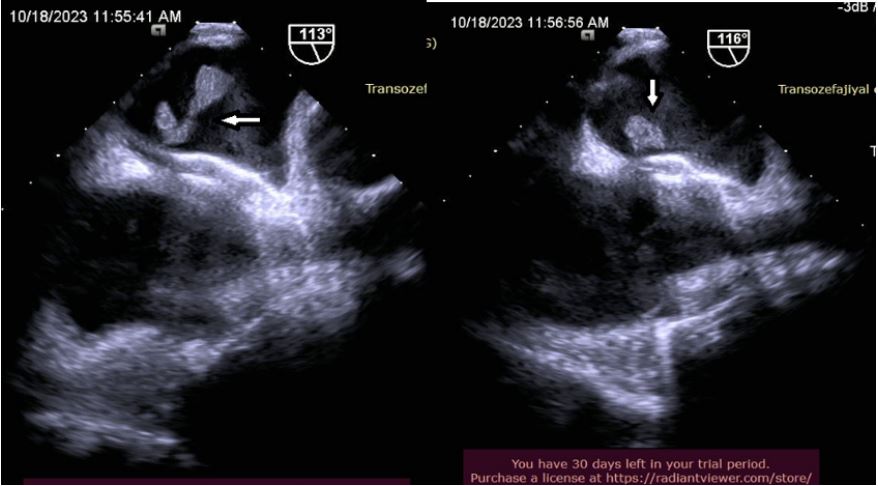

The diffusion MRI was taken after the patient re-applied to the emergency department of our center on 18/10/2023 with the complaint of speech impairment and numbness in the left arm. Acute infarction areas with sharply limited diffusion restriction with a long axis of approximately 5.5 cm in size were observed in the cortico-subcortical area at the ventricular level in the right cerebral hemisphere, in the temporoparital lobe, in the right cerebral hemisphere. Medical treatment was arranged according to the recommendation of neurology. In the TEE performed on the patient, an appearance consistent with a pedunculated mobile thrombus measuring 30*14 mm was observed on the left atrial side of the occluder device. After the patient was evaluated by the cardiology-cardiovascular surgery council, a surgical decision was made. The patient was discharged in full recovery after surgical treatment by cardiovascular surgery.

Figure 1